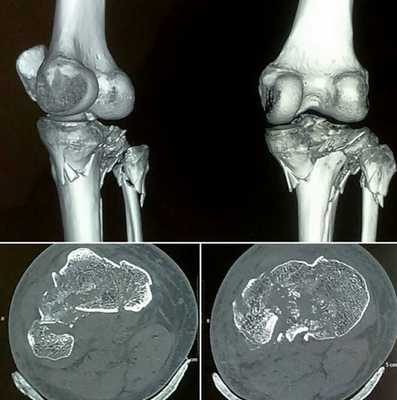

![Компьютерная томография колена]()

Компьютерная томография колена

![Остеосаркома бедренной кости на снимке коленного сустава]()

Остеосаркома бедренной кости на снимке коленного сустава

Для уточнения локализации и размеров патологического очага врач может использовать пространственное изображение области интереса . На основании фотографий, полученных в результате сканирования, реконструируют 3D-модель рассматриваемой зоны. Трехмерная визуализация позволяет оценить характер взаимодействия здоровых и пораженных тканей.